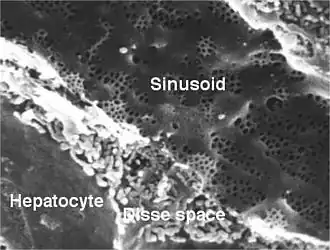

Microanatomy

Hepatocytes are organised into plates separated by vascular channels (sinusoids), an arrangement supported by a reticulin (collagen type III) network. The hepatocyte plates are one cell thick in mammals and two cells thick in the chicken. Sinusoids display a discontinuous, fenestrated endothelial cell lining. The endothelial cells have no basement membrane and are separated from the hepatocytes by the space of Disse, which drains lymph into the portal tract lymphatics.

Kupffer cells are scattered between endothelial cells; they are part of the reticuloendothelial system and phagocytose spent erythrocytes. Stellate (Ito) cells store vitamin A and produce extracellular matrix and collagen; they are also distributed amongst endothelial cells but are difficult to visualise by light microscopy.